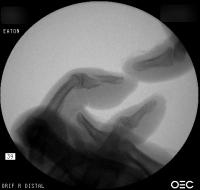

Case 3

Acute mallet fracture treated with percutaneous

pinning: proximal pin stabilizes the fracture

fragment, longitudinal pin maintains distal phalanx

position. |

| Thermoplastic bonding of the protruding ends: appearance at one month. |